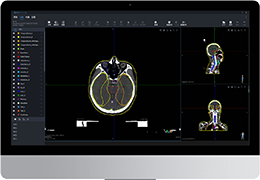

成像智能。

Eclipse 成像智能功能提供强大的处理能力和最佳质量的影像,同时减少质量错误并提高剂量效率。

凭借 AI、专有算法和先进的影像处理能力,提供出色的影像质量和无与伦比的诊断信心。

与标准影像处理相比,智能降噪功能可使客户降低辐射剂量,而不会损失影像质量。这在新生儿和儿科成像中尤其重要,在这种情况下以尽可能低的剂量成像至关重要。

提供相配视图选项,以减少所需的曝光次数,并提供更清晰的感兴趣区域视图。